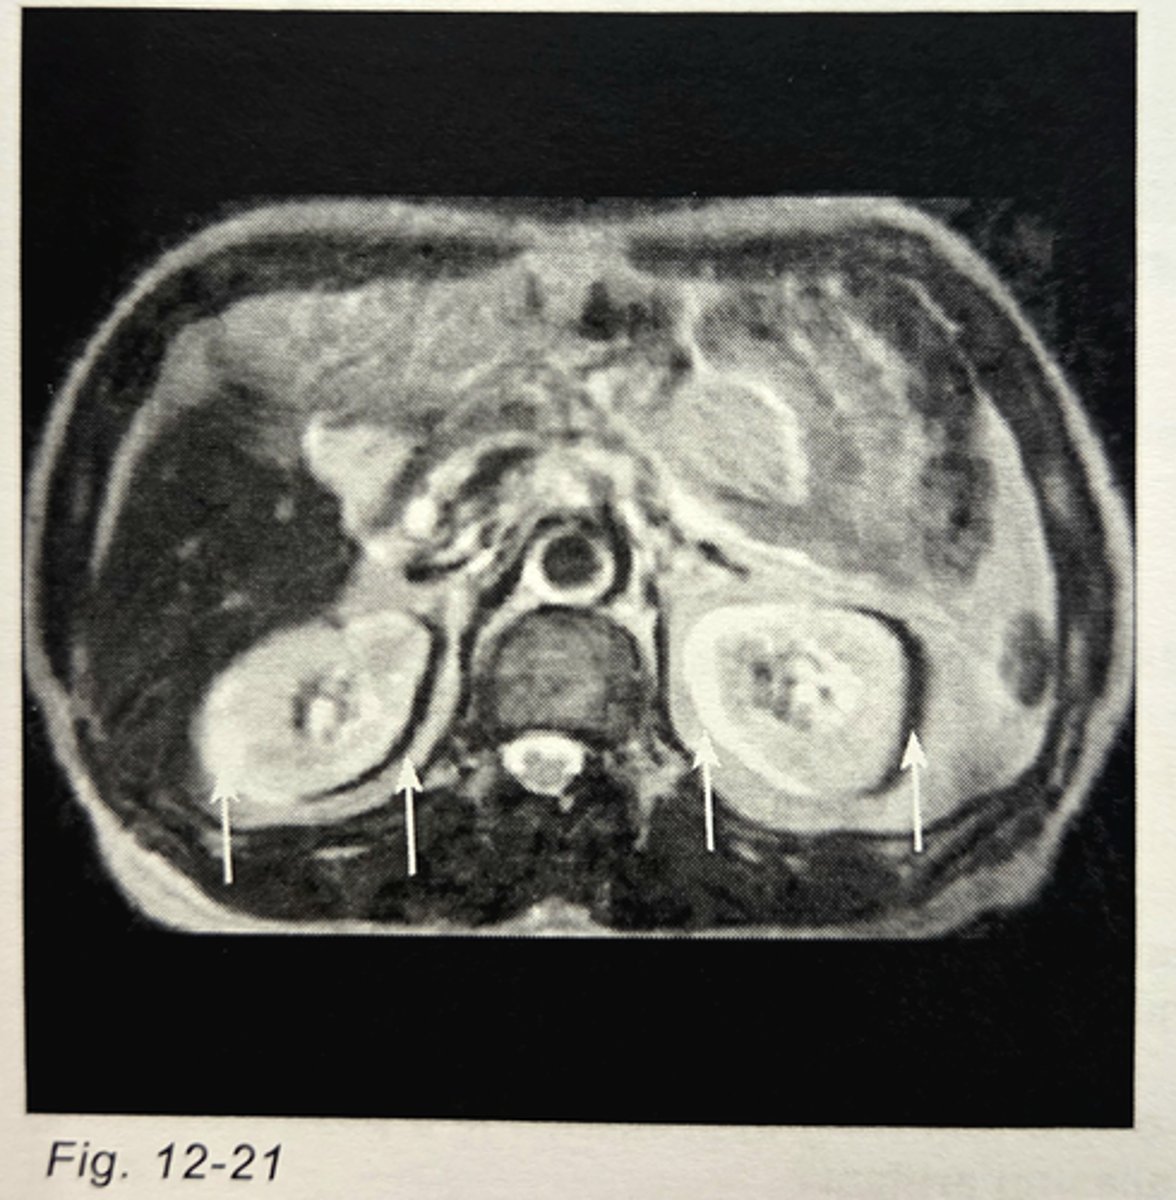

The image arrows in Fig. 12-21 are pointing to an example of _________________ artifact.

chemical shift

Which of the following is a method of reducing the artifact seen in Fig. 12-21?

increase the receiver bandwidth

Which of the following physical gradients is used for phase encoding in Fig. 12-21 (assume the coordinate convention at the beginning of the post-test section)?

y-gradient